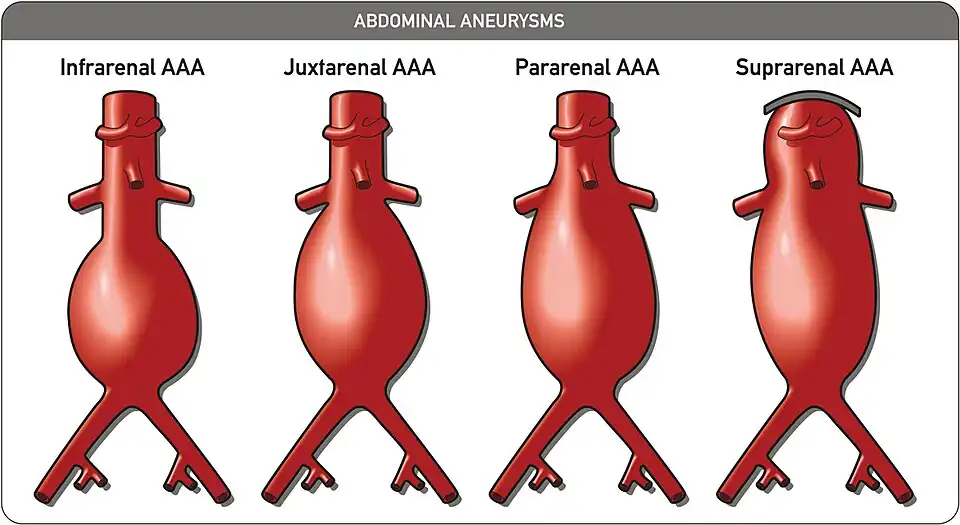

An abdominal aortic aneurysm (AAA) refers to aneurysmal dilation of the aorta confined to the abdominal cavity. Most commonly, aneurysms are asymptomatic and located in the infrarenal position. Often, they are discovered incidentally or on screening exams in patients with risk factors such as a history of smoking. Patients with aneurysms which have a diameter less than 5 cm are at <1% rupture risk per year. When the aneurysm meets size criteria it can be treated with aortic replacement or EVAR.

Abdominal aortic aneurysms can be classified as infrarenal, juxtarenal, pararenal or suprarenal as depicted in the illustration.

Abdominal aortic aneurysms can be classified as infrarenal, juxtarenal, pararenal or suprarenal as depicted in the illustration. -